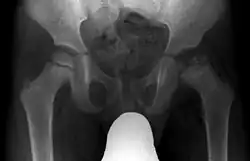

Radiograph of a person with Legg–Calvé–Perthes disease

X ray of deformity by Legg–Calvé–Perthes disease of the right hip (left side of X-ray)

Children younger than six have the best prognosis, since they have time for the dead bone to revascularize and remodel, with a good chance that the femoral head will recover and remain spherical after resolution of the disease.[19] Children who have been diagnosed with Perthes' disease after the age of ten are at a very high risk of developing osteoarthritis and coxa magna. When an LCP disease diagnosis occurs after age eight, a better outcome results with surgery rather than nonoperative treatments.[20] Shape of femoral head at the time when Legg-Calvé Perthes disease heals is the most important determinant of risk for degenerative arthritis; hence, the shape of femoral head and congruence of hip are most useful outcome measures.[7]